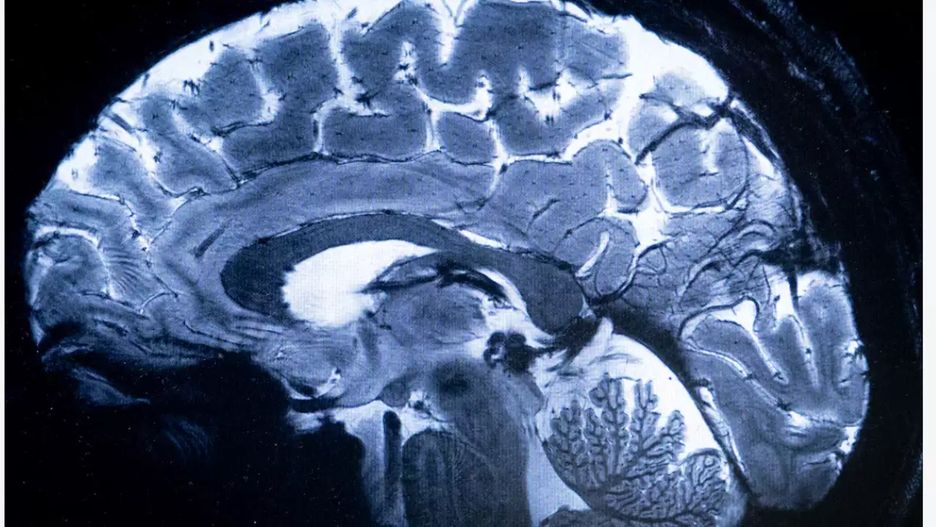

Najpotężniejszy na świecie skaner MRI rozpoczął pracę. Francuskie urządzenie do rezonansu magnetycznego wykonało pierwsze skany ludzkiego mózgu, zaprezentowane przez Francuską Komisję Energii Atomowej i Energii Alternatywnych (CEA).

Nowe urządzenie, zbudowane w ramach projektu Iseult po niemal 20 lat starań, oferuje 10-krotnie większą precyzję niż rezonanse magnetyczne stosowane powszechnie w szpitalach. Maszyna waży 132 tony i ma 5 metrów długości i 5 metrów szerokości.

Do budowy skanera użyto aż 182 km kabli, a rolę chłodziwa dla użytego w skanerze magnesu pełni 7,5 tys. litrów ciekłego helu. Skaner generuje pole magnetyczne o natężeniu 11,4 tesli i pozwala w krótkim czasie uzyskać obraz o bardzo wysokiej rozdzielczości.

Dzięki niemu możliwe jest uzyskanie skanu mózgu o rozdzielczości 0,2 mm i grubości warstwy 1 mm w czasie krótszym niż cztery minuty. Podobna szczegółowość skanu wykonanego przez zwykłą maszynę do rezonansu wymagałaby wielu godzin pracy urządzenia.